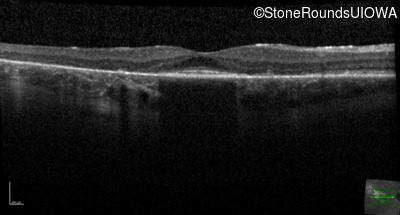

This 30 year old man first noticed poor vision in dim light when he was five years old. His visual acuity began to fall in his early 20's.

Diagnosis & molecular findings

Macular Disease WDR19 His344Arg CAT>CGT Ser485Ile AGT>ATT AR